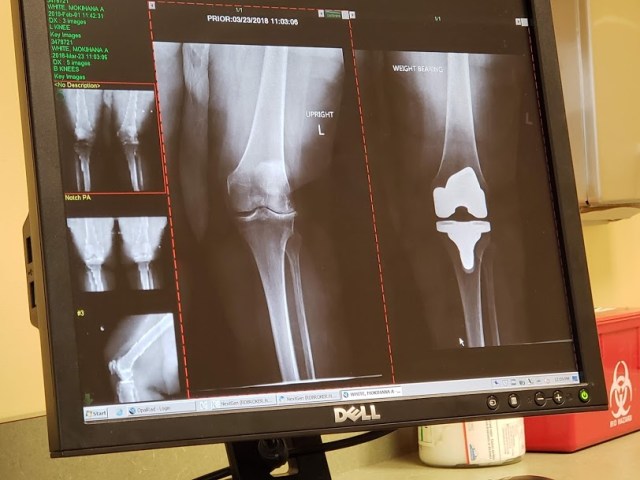

My orthopedic PT nurse showed me what my new knee looked like. Wowzie to da max. It really is pretty amazing.

I’m glad I had it done. It was a very difficult surgery and recovery because my surgeon, Dr. Borus, also had to straighten my crooked leg, which used to have quite an angle to it. See what I mean? Before x-ray on the left.